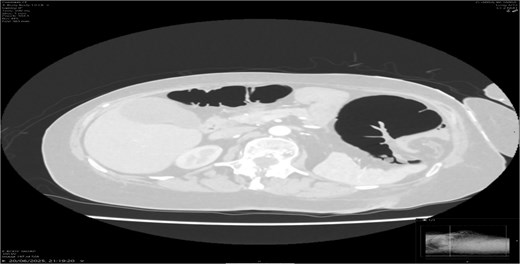

A contrast-enhanced CT scan of the abdomen demonstrated a whirl sign at the mesenteric root (Figs 1 and 2), dilated transverse colon with a transition point at the splenic flexure (Fig. 3), and no evidence of ischemia or perforation (Fig. 4). These findings were consistent with TCV.

Axial CT showing dilated transverse colon at the splenic flexure.